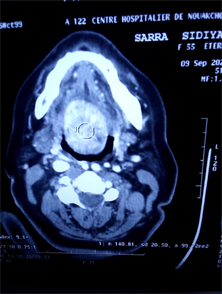

On clinical examination, a reddish mass at the base of the tongue is noted, of firm and well-defined consistency, with a homogeneous smooth surface and not bleeding on contact, taking the valves and coming into contact with the epiglottis (Figure 1). The cervical examination was without abnormality. The CT scan of the neck showed a strongly enhanced tissue mass by injection of contrast product in a homogeneous manner measuring 31 × 46 mm infiltrating the base of the tongue and the sublingual space arriving at the bottom in contact with the upper edge of the hyoid bone, occupying the valecules and extending to the level of the HTE space, responsible for a marked narrowing of the oropharynx (Figure 2(a) and Figure 2(b)).

Figure 2. Cervical CT scan: Axial section (a) showing enhancement homogeneous tumor after injection of contrast product. Sagittal section (b): the well-defined mass, reducing the die of the oropharynx.